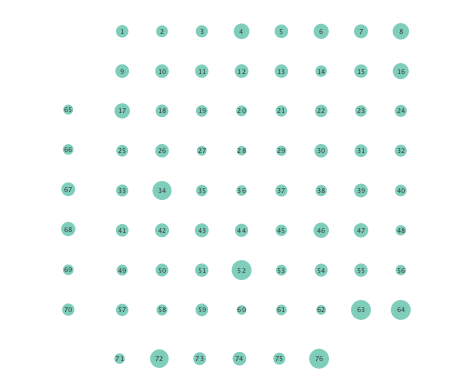

First, in- and out-degree was computed for nodes in each of the inferred networks. Note that the in-degree of a node counts its number of incoming edges, while the out-degree counts the number of out-going edges. The total degree per node sums the in- and out-degrees, and is indicative of how well-connected a given node is. Figure 3 depicts nodes in the network and their total degrees encoded by the radii of circles associated with the nodes. As expected from the previous subsection, Figures 3 (a) and (b) demonstrate that the linear SVARM yields both increases and deceases in the inferred node degree. On the other hand, the nonlinear SVARM leads to a more spatially consistent observation with most nodes exhibiting a smaller degree after the onset of a seizure (see Figures 3 (c) and (d)), which may imply that causal dependencies thin out between regions of the brain once a seizure starts.

In order to assess the information-routing abilities of brain regions before and after seizure onset, comparisons of the so-termed betweenness centrality were done. Betweenness centrality of a node computes the fraction of shortest paths between all node pairs that traverse the given node, and it is useful to identify the key information transmitting hubs in a network; see e.g., [24] for more details. The per-node betweenness centrality for each inferred network are depicted in Figure 4, with node radii similarly encoding the computed values. Little variation between preictal and ictal betweenness centralities is seen for the linear model (Figures 4 (a) and (b)), while variations are slightly more marked for the K-SVARM, see Figures 4 (c) and (d). It can be seen that modeling nonlinearities reveals subtle changes in information-routing capabilities of nodes between preictal and ictal phases.

Clustering coefficients are generally used to quantify network cohesion, the tendency for nodes to form groups or communities. Comparison of such coefficients between the preictal and ictal phases may reveal differences in cohesive behavior after onset of a seizure. In the present paper, a per-node clustering coefficient is adopted, and it computes the fraction of triangles in which a node participates out of all possible triangles to which it could possibly belong [24]. Note that a triangle is defined as a fully connected three-node subgraph. Figure 5 depicts clustering coefficients per electrode obtained during the ictal and preictal phases of the ECoG time series. While both the linear and nonlinear models yield changes in the computed coefficients, most nodes have lower clustering coefficients upon seizure onset in the networks inferred via the K-SVARM.

Finally, Figure 6 depicts the closeness centrality computed per node in the inferred networks. Closeness centrality measures how reachable a node is from all other nodes, and is generally defined as the reciprocal of the sum of geodesic distances of the node from all other nodes in the network; see also [24]. Once again, Figure 6 depicts a more general decrease in closeness centralities after seizure onset in networks inferred by the nonlinear SVARM, as compared to the linear variant. This empirical result indicates a change in reachability between regions of the brain during an epileptic seizure.

Moreover, the performance of K-SVARM with data-driven kernel selection was also tested. Figure 7 illustrates the per node degree as well as the closeness centrality of networks inferred from preictal and ictal phases. Consistent with Figures 3 and 6, Figure 7 again reveals universal decrease in node degrees as well as closeness centrality at seizure onset.